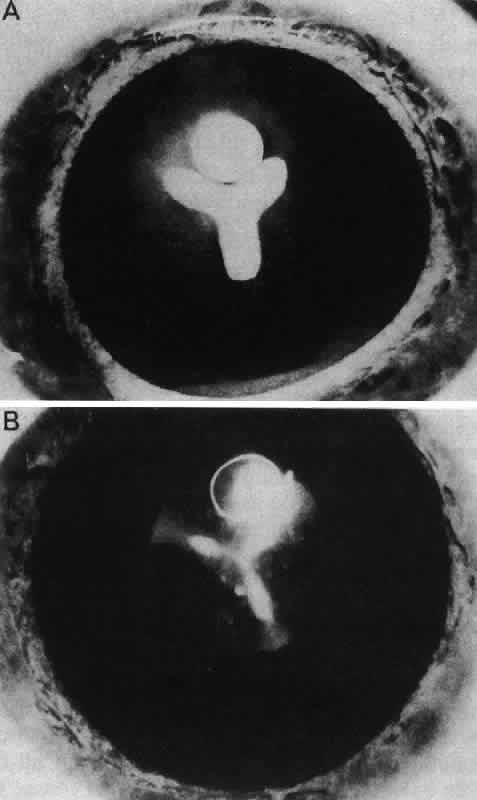

Retrolental Fibroplasia

Persistence of the hyaloid artery and the tunica vasculosa lentis may be associated with a pseudoglioma (pseudoretinoblastoma), an extensive connective tissue proliferation behind the lens. Two primary types, both rare, have been reported. One, retrolental fibroplasia, is primarily associated with infants born more than 8 weeks prematurely (i.e., before complete regression of the tunica vasculosa lentis) and is almost always bilateral. This may occur spontaneously or be associated with oxygen therapy in premature infants.175 Another type of pseudoglioma, persistent hyperplastic primary vitreous, may also occur as a unilateral condition in full-term infants. Dehiscence of the lens capsule is usually seen posteriorly, and the lens is sometimes cataractous.

Other opacities that fall under the category of capsulolenticular cataracts are the polar cataracts. In this case, the opacities are situated at either pole of the lens and generally involve only the superficial cortical area. The relatively common anterior variety assumes a number of forms but is typically plaquelike and circumscribed. The size of the opacity may vary from a small dot to one that occupies the entire pupillary region. Because it may have a laminate appearance, it has also been called a pyramidal cataract. Similar opacities are observed in children who have had corneal ulcers during infancy. The fact that the fetal nucleus of the lens is not involved suggests an occurrence relatively late in intrauterine life. Occasionally, an opacity might be seen above the previously incurred derangement separated by an apparently normal lenticular zone, producing the so-called reduplicated cataract. In this case, it is believed that, following an initial disturbance, normal fibers are deposited, followed later by a new, sometimes more severe disturbance that produces a second region of opacification. There are a number of variations on this theme, and such opacities may assume myriad possible forms. It may be significant that these opacities are often associated with a strand or strands of pupillary membrane that bridge the iris (in the region of the collarette) to the polar cataract.181–183 Similar adhesions to the pupillary margin have been noted. Another observation has been that these cataracts are often associated with signs of keratitis, most notably corneal opacification. It is interesting that, histologically, the changes are similar to those observed in the adult human lens following corneal ulceration.177–180 The polar cataract is typically associated with a hyperplasia of the epithelium and a great deal of necrosis of lens fibers in the subepithelial area.184 Multistratification of the epithelium occurs as the cells fill a depression left by the necrotic fibers (Figs. 36 AND 37). The cells become spindle-shaped and produce PAS-positive material. Contrary to a long-held but erroneous notion, the plaque thus formed does not represent a metaplastic transformation of epithelial cells into fibroblasts.185 The plaque is often undermined by normal cuboidal epithelial cells and is eventually surrounded by capsulelike material (see Figs. 36 AND 37). The most reasonable explanation of the basis of this anomaly is the development of intrauterine inflammation. Although it has been suggested that the anterior polar cataract may be the result of a persistent vascular tunic that interferes with nutrition, the counterpart, the posterior polar cataract, need not be associated with hyaloid remnants, yet the histologic picture is quite similar.